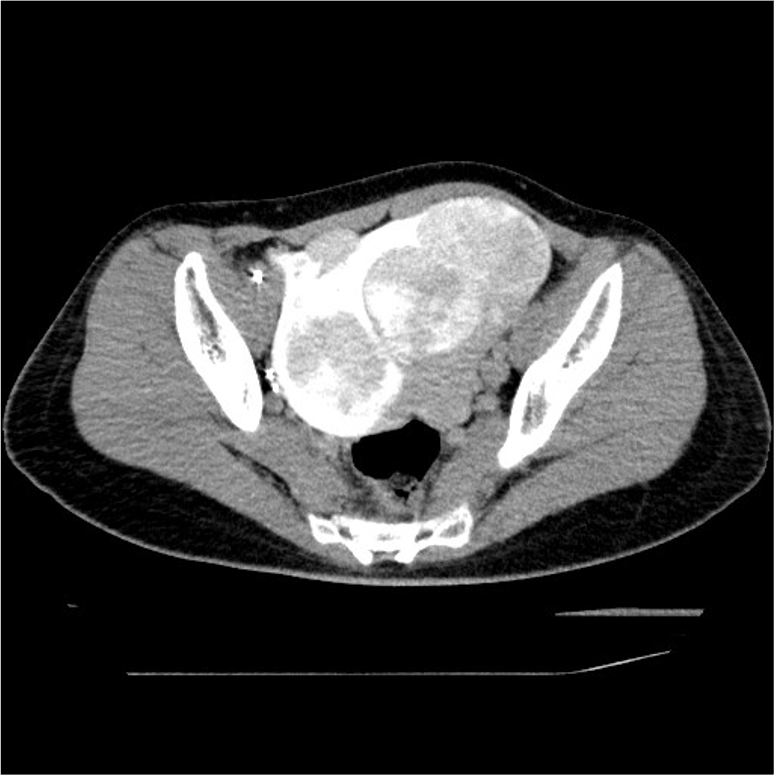

40歳代女性。過多月経、月経困難症状のある径95mm大までの多発子宮筋腫に対して子宮動脈塞栓術の依頼となり当科受診となった。塞栓物質注入開始前に、子宮筋腫の血流状態及び子宮卵巣動脈吻合の有無の確認目的で子宮動脈からの血管造影下CT(CT Uterine Arteriography (CTUA))を撮像した。

子宮筋腫に対する子宮動脈塞栓術(UAE)は、症候性の子宮筋腫で、挙児希望のない閉経前の女性に対して行われる。カテーテルを用いて子宮動脈から塞栓物質を注入し、子宮動脈の塞栓を行う手技である。

UAEの合併症には下腹部痛、術後感染、筋腫の子宮内腔脱落の他に、卵巣機能不全(45歳未満:0-3%、45歳以上:20-40%1))、非標的塞栓などがある。そのため、UAEを施行する際には、術前にMRIやCTにより子宮筋腫の局在や血管走行を確認してから治療を行う必要がある。我々は血管造影時に選択的子宮動脈造影と血管造影下CT (CT Uterine Arteriography :CTUA)を施行することにより、卵巣の濃染の有無や、拡張した子宮卵巣動脈吻合の有無、膣や子宮頸部の濃染の有無を確認し、UAEを施行している2)。Type1BやType3の子宮卵巣動脈吻合3)がみられた場合、UAEにより塞栓物質が子宮卵巣動脈吻合に流入し、卵巣機能不全に陥る可能性がある。そのためCTUAにより子宮卵巣吻合の分岐を確認し、子宮卵巣吻合のType分類を行い、子宮卵巣吻合が太く、卵巣への血流が豊富な場合(Type1B,Type3)には、子宮卵巣動脈吻合のコイル塞栓を施行している。CTUAを施行することにより、塞栓物質の非標的塞栓や子宮卵巣動脈吻合への塞栓物質の流入を防ぎ、安全にUAEが可能である。